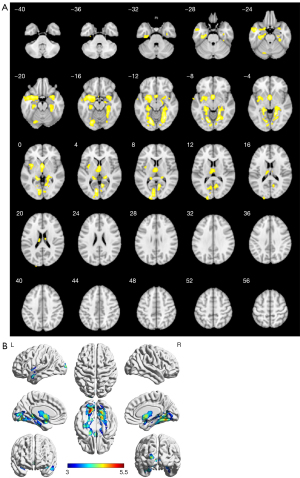

Compared with the NC group, GMV decreased in the left lingual gyrus, parahippocampal gyrus, fusiform gyrus, talar fissure, hippocampus, insula, middle temporal gyrus, and dorsal thalamic nucleus in the CSVD-CI group and decreased in the right temporal pole, fusiform gyrus, parahippocampal gyrus, fusiform gyrus, amygdala, and dorsal thalamic nucleus, with the most significant reduction in the left lingual gyrus, the dorsal thalamic nucleus, and the right lingual gyrus as well as the amygdala, and no volume increase in brain regions (P<0.001 at the voxel level, cluster >910 corrected for cluster level FWE, as shown in Figure 1 and Table 3).

Table 3

| Structure | Peak MNI coordinate (mm) | Voxels/cluster | t | ||

|---|---|---|---|---|---|

| X | Y | Z | |||

| Lingual_L | −10.5 | −76.5 | 3 | 1,520/9,389 | 5.23 |

| Lingual_R | 18 | −48 | −6 | 1,487/4,734 | 5.01 |

| Amygdala_R | 30 | 6 | −18 | 188/910 | 4.11 |

| Thal_MDm_L | −1.5 | 0 | 0 | 212/2,063 | 4.48 |

The peak point is the point with the greatest difference in the different brain regions. MNI coordinates: a three-dimensional human brain localization space developed by the MNI, Canada. P<0.001, cluster level FWE correction, cluster ≥910. CSVD, cerebral small vessel disease; FWE, family-wise error; GMV, gray matter volume; MNI, Montreal Neurological Institute; VBM, voxel-based morphometry.

The VBM technique enables voxel-level quantitative analysis of gray and white matter volumes by means of morphological segmentation algorithms with high-resolution T1WI to localize gray matter atrophy that is significantly correlated with executive function, memory encoding, and processing speed. Brain atrophy and CI can also be detected early in the onset of CSVD. The VBM analysis in this study showed that gray matter atrophy in patients with CI in CSVD mainly ranged from the bilateral temporal lobe, occipital lobe, and thalamus, with significant atrophy in the lingual gyrus, amygdala, and thalamus mid-dorsal nucleus of the cortex, as compared with that in the group with no CI in CSVD. It has been shown that patients with CSVD may be accompanied by extensive volumetric atrophy of cerebral gray matter (24,25). It may occur independently of white matter, but the underlying cellular mechanisms that allow structural changes in specific brain gyrus regions have not been fully investigated. It has been shown that extensive degeneration of GM structures in CSVD patients, especially bilateral temporal lobe and hippocampal volume atrophy, is closely associated with CI (26,27). In addition, brain regions with reduced GMV in VCI patients with varying degrees of CI were also found in the frontal, parietal, and limbic brain regions. The results of the present study are not entirely consistent with those of previous studies. This study suggests that cognitive deficits in patients with CI in CSVD may be accompanied by temporal lobe and thalamic atrophy, which may produce cascading damage and consequently abnormal coupling of deep gray matter and functional structures.